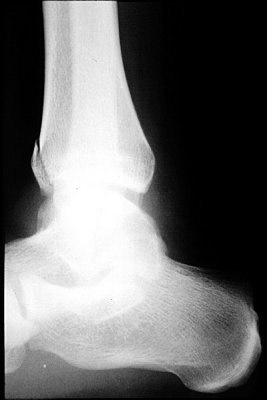

Return to Tillaux Fracture